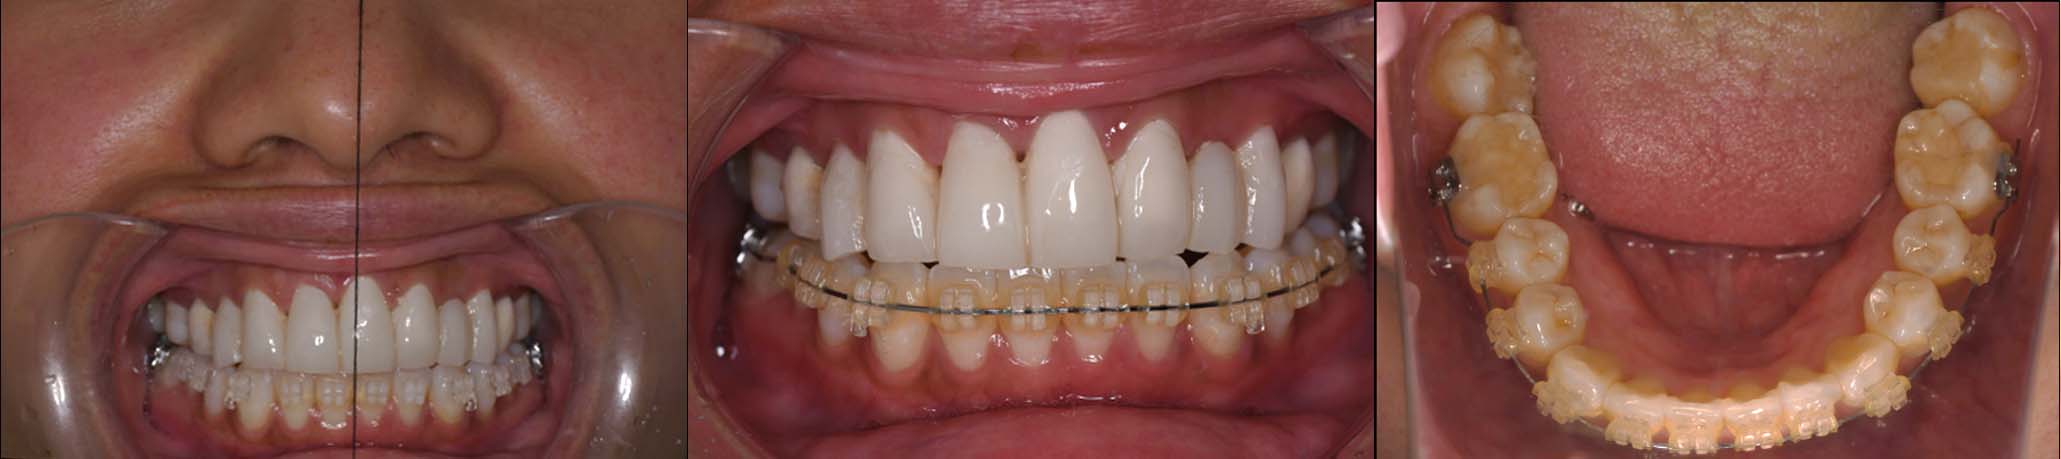

噛み合わせ治療の症例24

スプリント使用後、

補綴治療をした症例

| 治療内容 | ①スプリントを装着 ②副子を装着 ③2024年4月 口腔内反映開始 ④副子を入れた状態の所まで咬合を挙上 (バイトアップ) ⑤2024年5月 上顎前歯部8本へ仮歯(TEK) を装着 |

バイトアップ後

2024年 10月 下顎MTM開始